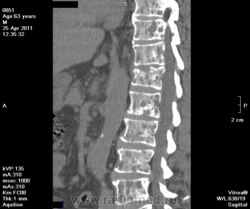

Миеломная б-нь?

Множественные метастазы, к которым условно можно отнести и миеломную болезнь. Коль это мужчина надо посмотреть простату и назначить консультацию гематолога. Жаль, что Вы не указываете возраст и клинические данные.

возраст указан на снимках - 63 года, направлен с диагнозом вертеброгенная торако-люмбалгия, выраженный болевой стойкий синдром ст.обострения. Жалобы на сильные боли в нижнегрудном и поясничном отделе позвоночника, скованность в спине. Болен около 4х месяцев

со стороны черепа таких выраженных изменений нет - остеопороз, расширены диплоэ, кое где кисты

хотелось бы уточнить - метастазы или таки миеломная болезнь?

Исключить миелому можно только с помощью стернальной пункции.

Но может быть любое миелопролиферативное - растущее в красном костном мозге - заболевание - метастазы, болезни крови и т.п. - дальнейшая диагностика - по пунктату, фракциям глобулинов, поску первичной опухоли...

предстательная железа обычной формы 38мм в передне-заднем размере. Мочевой пузырь - стенки ровные, четкие, не сдавлен.

мало вероятно, что простата даст такое количество литических очагов. Легкое, почки. Хотя и почки в таком количестве сложно представить.

На мелкоклеточный рак легкого можно подумать. И конечно, кровь, смотреть. Уж слишком обширное поражение костного мозга, м.б. системным

Феохромацитома может давать такие мета, и необязательно из надпочечников...